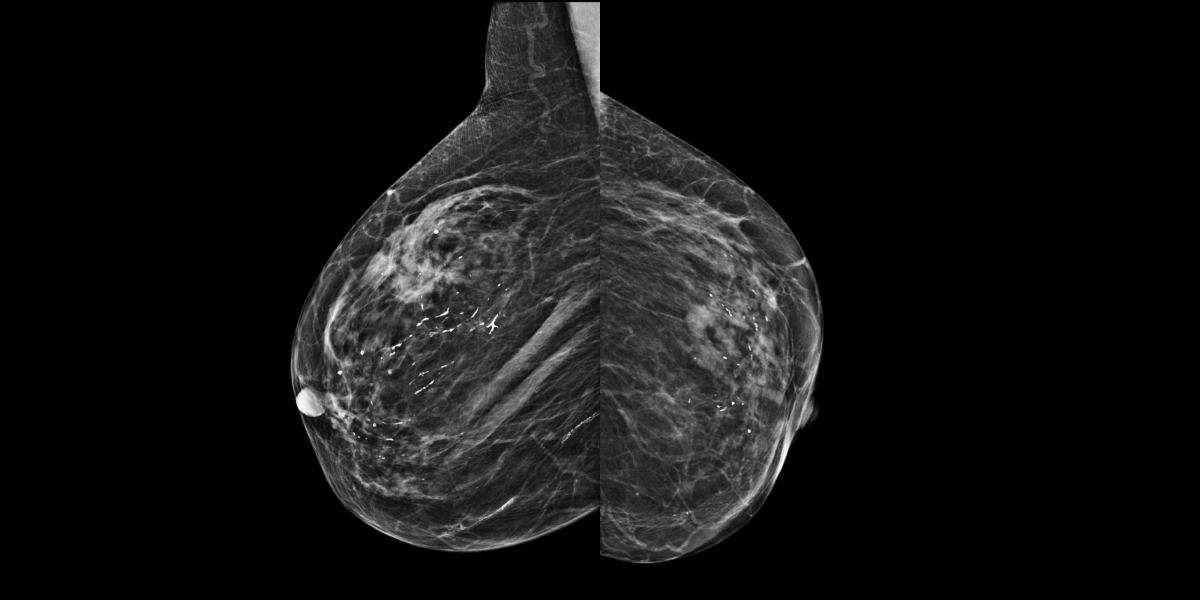

Patiente de 74 ans, une mammographie est réalisée pour exploration d’un nodule supéro externe du sein droit.

MammoScreen™ pointe une opacité spiculée du quadrant supéro externe du sen droit mais egalement une anomalie externe du sein gauche.

L’échographie confirme une formation lobulée hypoéchogène à l’union des quadrants externes du sein droit et une formation nodulaire hypoéchogène à l’union des quadrants inférieurs du sein gauche présentant une rigidité à l’étude élastographique.

La microbiopsie confirme des carcinomes canalaires infiltrants RH+, Her2+ faible.